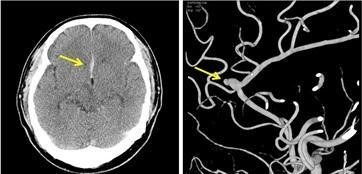

‘뇌혈관질환’ 중 뇌출혈 환자는 2007년 7만1,943명에서 2012년 8만493명으로 1.1배 증가한 반면 뇌동맥류 환자는 2007년 1만 2,446명이었던 것이 2012년에 3만 9,603명으로 3.2배 증가하였고, 인구 10만명당 환자수도 2007년 26명에서 2012년 80명으로 2007년 대비 3.1배 증가하였다.

양교수는 “뇌동맥류 환자가 급증하는 것은 질환 자체의 증가보다는 최근 들어 진단기술의 발달(MRI 등)로 기존에 진단하지 못했던 경우가 가능해졌기 때문으로 생각되며, 대개 뇌동맥류는 100명당 약 1명에서 발견된다고 알려져 있고, 뇌동맥류를 가진 환자의 1~2%정도에서 출혈을 일으키는 것으로 알려져 있다“고 설명하였다.